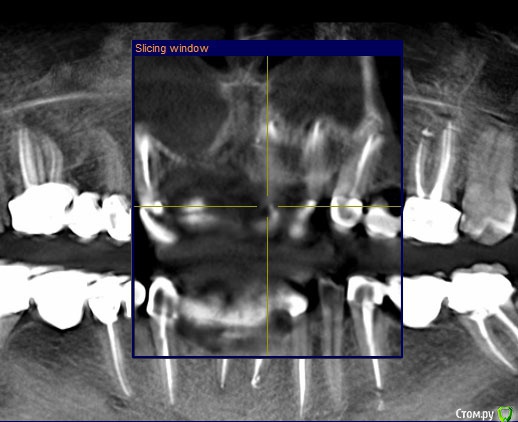

ira. k.. 78 Опубликовано 12 мая, 2020 Поделиться Опубликовано 12 мая, 2020 Здравствуйте уважаемые доктора. Хочу у вас спросить. Зуб клык слева (23), немного стала чувствовать дискомфорт в нем, зуб стоит с штифтом 14 лет, коронку сменила год назад, было всё хорошо, зуб не перелечивали, сделала кт в марте 2020, и увидела у коня немного затемнения, а врач сказал всё хорошо, подскажите, что это, и что с этим делать, мост не хотелось бы снимать, ему только год. Ссылка на комментарий

kramer Опубликовано 12 мая, 2020 Поделиться Опубликовано 12 мая, 2020 Срезы неудачные Ссылка на комментарий

It'sGeorgy Опубликовано 12 мая, 2020 Поделиться Опубликовано 12 мая, 2020 (изменено) ну если прямо сильно нажимаю на него то ощющение небольшой боли вроде есть, а так кушать не больно им, а что скажите по кт, я в срезах не понимаюНа КТ, действительно, есть очаг разрежения костной ткани вокруг этого зуба. При этом, сказать, что каналы запломбированы плохо - тоже нельзя. Я не терапевт, но со своей точки зрения вижу ситуацию так, что у зуба, на самой вершине, есть достаточно выраженный изгиб, что создало огромную трудность для доктора, который зуб лечил. Этот изгиб, к сожалению, запломбировать ко конца не получилось, что привело к развитию хронического воспаления.Повторюсь, я подобным лечением не занимаюсь и мое мнение может быть ошибочным. Поэтому, предлагаю подождать, пока вам ответит кто-то из здешних терапевтов. это не может быть от зуба?Такие ситуации могут быть от зуба, но тогда боль острая и постоянная. Плюс, тогда пациент сам может определить, что его беспокоит конкретный зуб. В вашем случае, как я понимаю, такого нет. Да и судя по снимку, остальные верхние зубы слева в порядке. делала кт 3 раза за годЕсли есть возможность, выкладывайте их тоже. Потому, что на снимке, который вы выложили очень много фоновых шумов, которые создают металлические конструкции во рту(мостовидные протезы). Возможно, по снимкам до изготовления постоянных конструкций будет видно и понятно лучше. Изменено 12 мая, 2020 пользователем It'sGeorgy Ссылка на комментарий